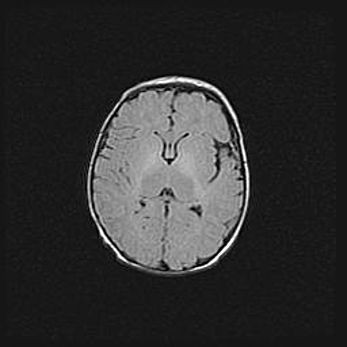

Лейкомаляция с кистозно-глиозной дегенерацией головного мозга.

Возраст: 2 месяца 25 дней

Вес: 6400 г

Окружность головы: 40 см

Срок гестации: 41 неделя

Лейкомаляцию относят к ишемически-гипоксическим повреждениям головного мозга, диагностируемым у новорожденных. При лейкомаляции в головном мозге обнаруживают очаги некроза, возникшие после тяжелой гипоксии и нарушения кровотока. В процессе морфогенеза очаги проходят три стадии: 1) развития некроза, 2) резорбции и 3) формирования глиозного рубца или кисты. Перивентрикулярная лейкомаляция (ПЛ) встречается примерно в 12% случаев среди новорожденных, обычно – у недоношенных детей, причем, частота ее зависит от массы, с которой младенец появился на свет. Наибольшее число малышей страдает лейкомаляцией, если масса при рождении 1500-2500 г.